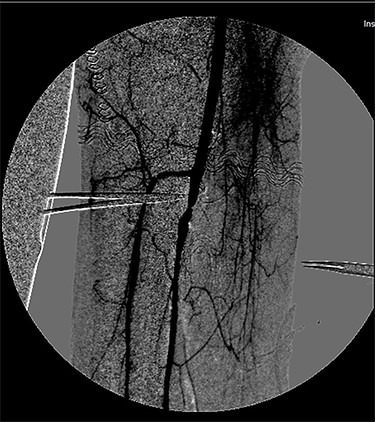

During hospitalization, the patient underwent many orthopedic surgeries for various fractures of the right lower limb, and a centimetric pseudo-aneurysm of the right SFA (Fig. 1), was found at a routine duplex ultrasound of the lower limbs, originating from a small collateral branch of SFA at the distal third of the thigh.

Preoperative angiography showing the pseudo-aneurysm of the right SFA, originating from a small collateral branch of SFA at the distal third of the thigh.